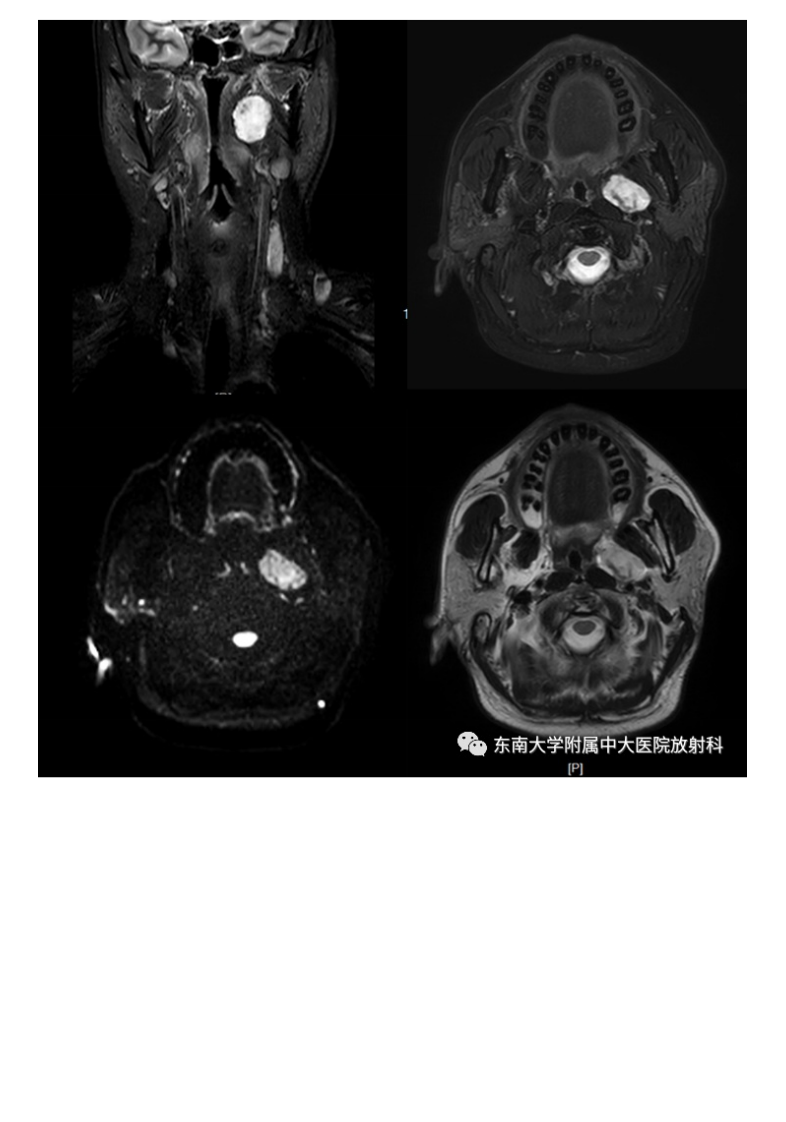

20210617_2【晨读结果公布】2021.06.17头颈部疾病——多形性腺瘤.pdf